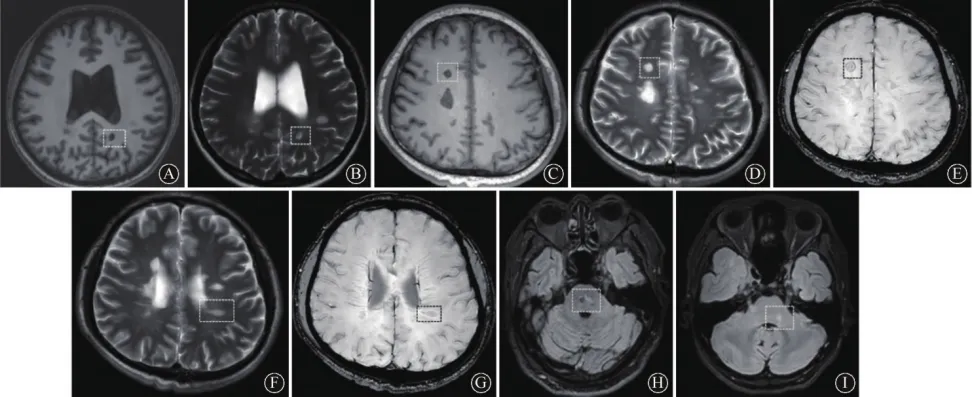

注:MS,多发性硬化;CSVD:脑小血管病;SWI,磁敏感加权成像;A,MS患者 T1像上可见左侧侧脑室脚处有一“黑洞”状低信号(方框内所示);B,MS患者“黑洞”在 T2像上呈高信号;C~E,MS患者 T1像可见低信号(C)、T2像高信号病灶(D)、SWI上的铁环征(E)(方框内所示);F~G,分别为中心静脉征在 T2像和SWI像上的表现;H,CSVD 患者 Flair像可见脑桥病变位于脑桥中间(方框所示);I,MS患者Flair像显示脑桥病变位于脑桥边缘(方框所示)。

图 1 多发性硬化和脑小血管病患者的影像学特征